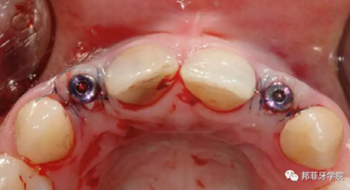

牙齦成型器周圍應(yīng)嚴(yán)密縫合,防止唾液進入切口(圖9)。X線片顯示植體位置理想(圖10)。愈合期未見并發(fā)癥,植體周圍牙齦愈合良好(圖11)。十周后取模,椅旁制備臨時牙(圖12),并制作螺絲固位PEEK基臺。

圖 9:上牙齦成形器并嚴(yán)密縫合